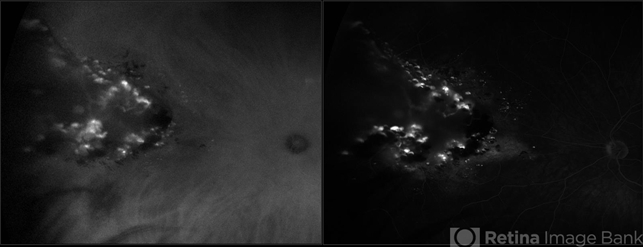

- ultra-wide field imaging, cavernous hemangioma of the retina, Optos, fluorescein angiogram (FA), indocyanine green (ICG) angiography, late phase, left eye

- Ultra-widefield fluorescein and ICG angiogram of a 31-year-old male presenting with a retinal cavernous hemangioma affecting his left eye. Patient was 18-years-old when he was diagnosed with a retinal cavernous hemangioma. He has had a few episodes of vitreous hemorrhages since then. His vision was 20/20-1 in both eyes.